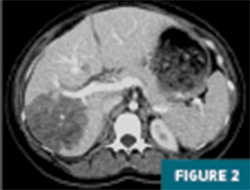

CT imaging of the abdomen and pelvis with IV contrast revealed a 12.5 cm geographic region of hypo-enhancement in the right hepatic lobe, without associated mass effect on adjacent liver parenchyma or vasculature (Figures 1-3).

On CT imaging, infarction typically presents as an ill-defined, geographic, often wedge-shaped area of hypodense parenchyma, mostly peripheral without mass effect on adjacent structures on postcontrast images. On MR imaging, regions of hepatic infarction appear as hypointense lesions on T1 imaging, with heterogeneous areas of hyperintensity on T2 imaging.